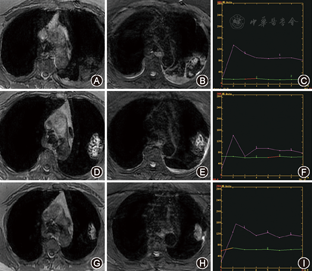

两名阅片者T1WI和T2WI评分一致性检验的Kappa值为0.872、0.856,一致性非常好。根据评分情况(表1),术后1 d,16个消融区(61.5%)呈T1WI等信号、19或20个(73.1%,76.9%)呈T2WI稍高信号(图1A,图1B)。术后1周,22个(84.6%)呈T1WI高信号,17个(65.4%)呈T2WI高信号,22个(84.6%)边缘有完整低信号环(图1D,图1E)。术后1个月,17个(65.4%)为T1WI高信号(图1G),两名阅片者分别评价22(84.6%)和21(80.8%)个为T2WI高信号(图1H)。术后3~12个月,消融区呈T1WI及T2WI等信号改变。术后1 d,26个消融区均混杂信号,随时间延长信号逐渐变均匀。术后1周信号强度最高,而后逐渐下降,术后3~12个月呈等信号(表2)。

术后1 d消融区最大径为(56±23) mm,而后逐渐缩小。术后1 d~1个月,消融区未见明确强化,时间-信号曲线呈直线型(图1,表2),术后3~12个月,呈轻度延迟强化的"流入型"(图2,表2)。术后3个月,19个(73.1%)呈楔形,7个(26.9%)呈类圆形(图2A,图2B)。